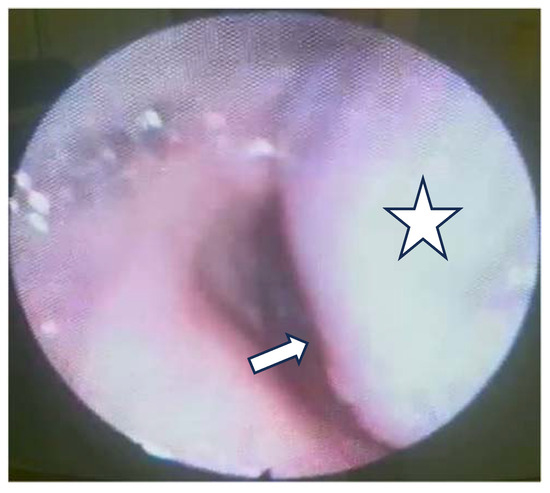

A tumor of 30/30 mm was resected and was sent to the anatomic pathology department (Figure 7). The histological result confirmed the diagnosis of a laryngeal paraganglioma.

Figure 7.

The resected tumor.